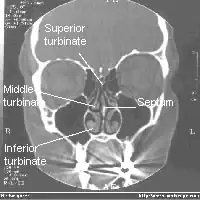

![]() Tomografía axial computarizada frontal del cráneo mostrando los senos paranasales. | ||